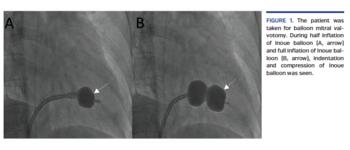

A 50-year-old Indian woman who was a laborer by occupation presented to the emergency department with gradually progressive exertional dyspnea from New York Heart Association class II-IV for 15 years. She was married and had 2 children with uneventful deliveries. The physical examination revealed a grade III parasternal heave, a loud S1, a pansystolic murmur (grade 4/6) at the left lower sternal border, and a low-pitched, long diastolic rumble at the apex. Transthoracic echocardiography revealed very severe mitral stenosis (calculated valve area by planimetry, 0.8 cm2; normal, 4-6 cm2) and severe tricuspid regurgitation with mild pulmonary hypertension. Her Wilkin’s score was 8/16 (subvalvular = 3, mobility = 2, calcification = 1, leaflet thickening = 2). After proper consent, she was taken for balloon mitral valvotomy. During half inflation of the Inoue balloon (Figure 1A) and full inflation of the Inoue balloon (Figure 1B), indentation and compression of Inoue balloon was seen (Video 1), which is indirect evidence of severe subvalvular disease. There were no intraoperative complications. The mitral valve increased to 1.3 cm2 and mean left atrial pressure decreased from 25 mm Hg to 8 mm Hg (normal, 8 mm Hg). Severe subvalvular disease predicts poor outcomes in balloon mitral valvotomy.